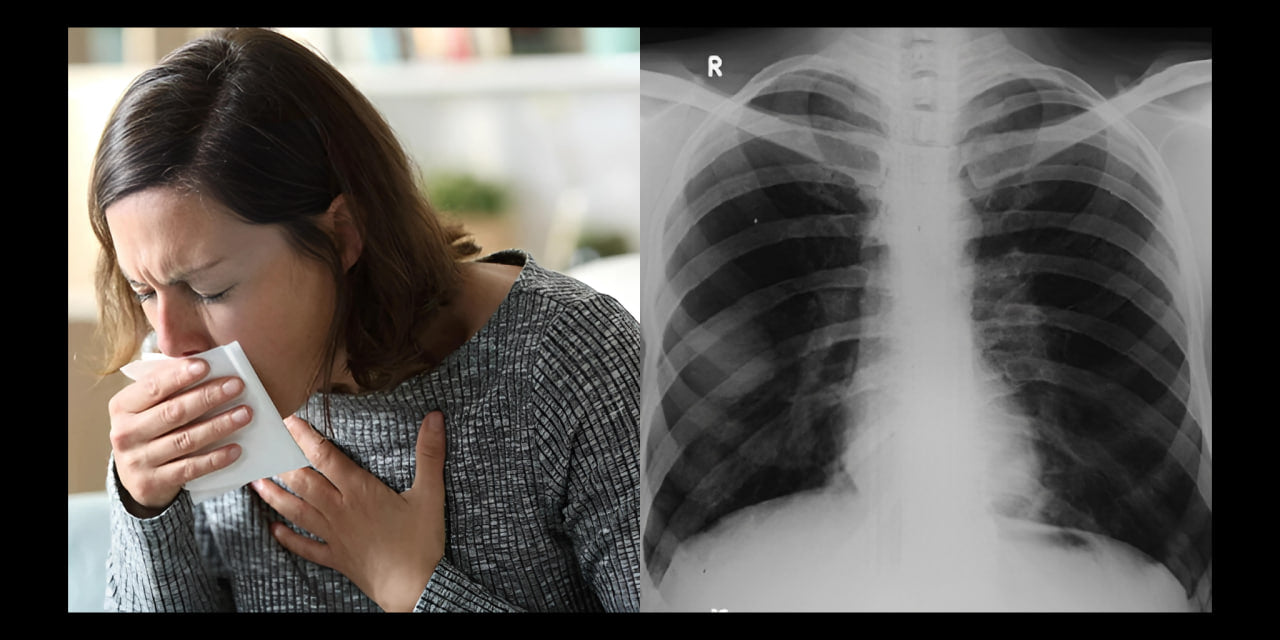

How I went from shortness of breath and coughing to breathing easily

Are you often short of breath, have a cough or feel that your lungs are not functioning optimally? Even though your doctor may reassure you that everything is fine, you are still left with symptoms. Discover my story here and find out the positive changes I have made to my life.

My name is Francesca van Vught, and for over four years, I suffered from coughing, breathing problems, and shortness of breath.

During this time, I visited several doctors and underwent the necessary tests. I repeatedly heard that my lungs looked good and I had nothing to worry about.

I am well aware that smoking cannot positively affect my symptoms. During my doctor visits, I was frequently told that smoking can lead to serious lung problems, including COPD (Chronic Obstructive Pulmonary Disease).

This progressive lung disease can permanently damage the airways, making breathing increasingly difficult.

Yet, no doctor had ever been able to tell me precisely where my symptoms stemmed from. COPD did not immediately emerge from the examination results as a possible cause.